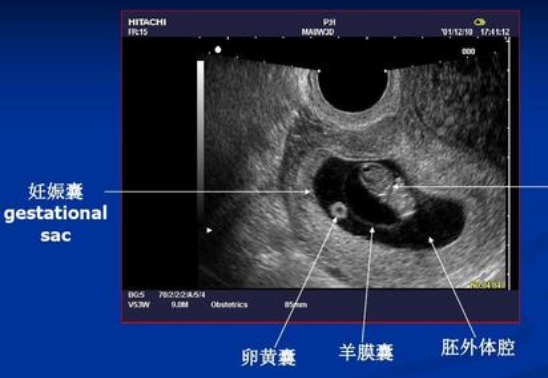

那更准确的方法,是通过做B超,看胎儿的大小,并且测量一些数据,根据这些数据来计算胎儿怀了多少天(几周)了。

比如在

怀孕早期

,根据孕囊的大小、胎芽的长度来判断怀孕多少周了。

胎儿发育有规律,不同孕周的胎芽长度不同,检查后,医生只需要对应从表格里找胎芽对应的孕周就可以了。